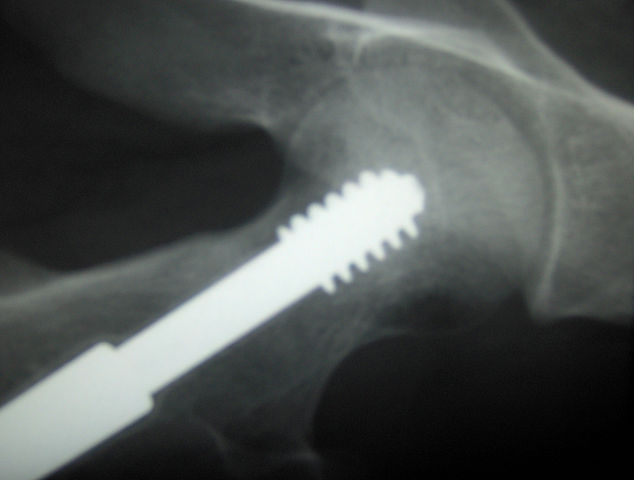

En photo : un implant orthopédique vu au Rayon X / CC Wikimédia